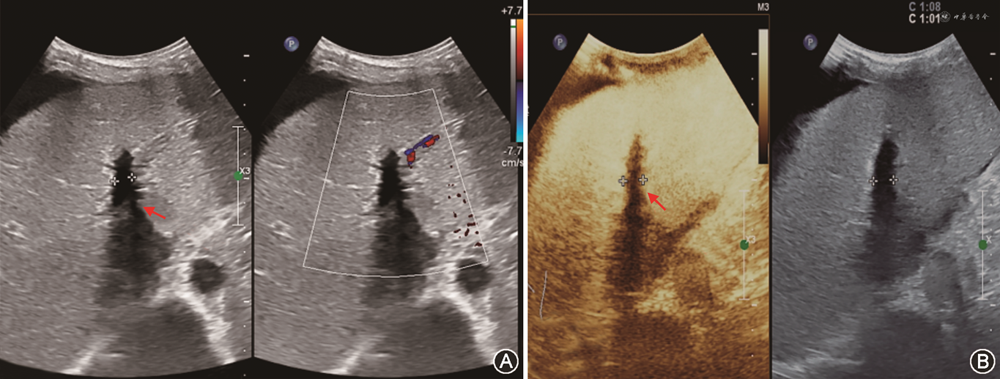

(2)胆道狭窄:胆道狭窄包括吻合口狭窄和非吻合口狭窄。吻合口狭窄较常见,多表现为手术吻合口附近5 mm内的孤立狭窄,与吻合技术不当有关,其中位发生时间是移植术后5~8个月。非吻合口狭窄指距离手术吻合口>5 mm的不规则狭窄,可在肝门部或肝内胆管多处发生,多与胆管缺血有关,故又被称为缺血性胆道病变[82,86],发生时间多在移植术后3~6个月。吻合口狭窄声像图主要表现为胆管吻合口处狭窄伴肝内胆管规则连续扩张;超声还可显示因狭窄导致胆汁引流缓慢而出现的胆泥或结石;经胆道超声造影对显示肝外胆道狭窄的部位及程度有一定价值[3]。缺血性胆道病变时,CDFI检查示肝内胆管为跳跃性、节段性不规则扩张,可合并胆管铸型、胆汁瘤及胆漏(图19);超声造影检查可观察到肝门部胆管壁动脉期无增强或低增强,以该特征诊断缺血性胆道病变的灵敏度、特异度及准确性分别为66.7%、88.9%及76.2%[86, 87]。需注意,超声检查发现移植肝胆道狭窄时,应同时检查肝动脉通畅情况,排除肝动脉并发症可能[88, 89]。MRCP能清楚显示包括胆道狭窄段的胆管全程,诊断胆道狭窄阴性预测值高。因此,评估移植肝胆道狭窄,超声与MRCP联合应用更有诊断价值[90, 91]。